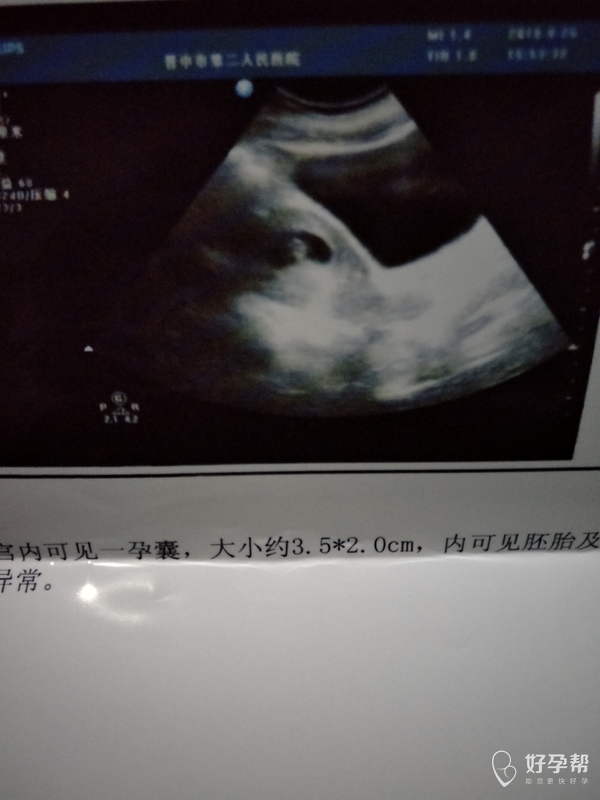

怀孕50多天 有胎心胎芽啦!

怀孕五十天b超单

怀孕50多天了,今天去做的b超